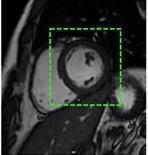

3. Évaluation de la sarcoïdose : il s’agit d’une maladie qui se caractérise par la formation anormale de tissu (granulomes) dans divers organes, dont le cœur (figure 1 ). Le recours à la TEP-FDG cardiaque dans les cas de sarcoïdose cardiaque est particulièrement important compte tenu du fait que le diagnostic de cette maladie peut être difficile. Les symptômes de la sarcoïdose cardiaque sont souvent vagues et peuvent être confondus avec ceux d’autres maladies comme l’insuffisance cardiaque ou la myocardite. En outre, les techniques d’imagerie traditionnelles, comme les échocardiogrammes et les IRM, peuvent ne pas être en mesure de détecter les premiers stades de cette maladie. Les granulomes observés dans les cas de sarcoïdose peuvent souvent être très inflammatoires, ce qui permet de les détecter à l’aide de la TEP-FDG cardiaque. Outre son utilité dans le cadre du diagnostic, la TEP-FDG cardiaque se révèle également utile pour guider le traitement chez la patientèle atteinte de la sarcoïdose. Le recours à la TEP-FDG cardiaque dans les cas de sarcoïdose cardiaque est une technique encore relativement nouvelle

Figure 1 : Exemple de TEP-FDG chez une personne atteinte de sarcoïdose cardiaque. Outre la détection de l’inflammation du myocarde, la TEP-FDG du corps entier permet de détecter les emplacements atteints à l’extérieur du cœur et d’obtenir davantage d’information sur le stade de la maladie.